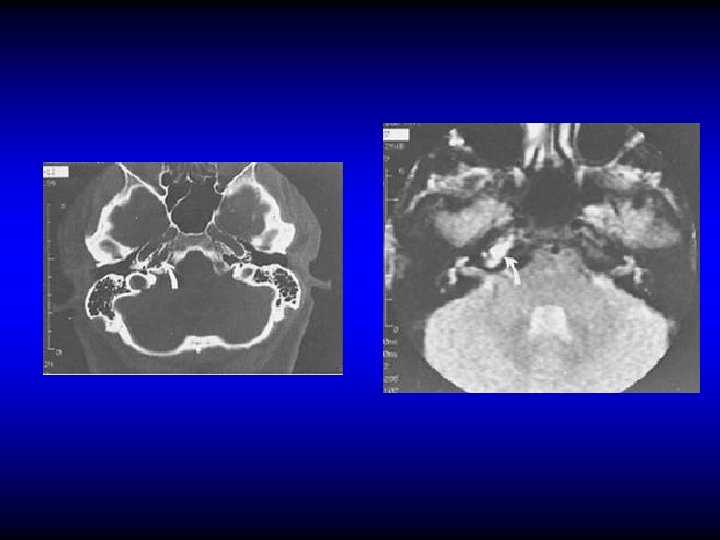

LATERAL SINUS THROMBOPHLEBITIS • • Diagnosis Fever, rigor, and sweating Headache and neck pain Tenderness and edema in the neck Manifestation of increased IC pressure Propagation and embolic manifestations Blood culture, CSF manometry CT, MRI

CT Subtraction Angiogram MRI Angiogram